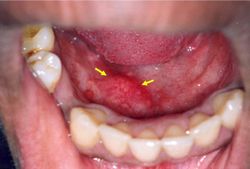

N’importe quelle glande salivaire peut faire un calcul qui obture partiellement ou totalement le canal excréteur, même les glandes salivaires accessoires.. La symptomatologie est généralement assez claire, car la salive est surtout sécrétée au moment des repas et c’est donc à cette occasion que les douleurs et les gonflements vont se manifester. En fonction du siège de la douleur et de la tuméfaction, on peut avoir une idée de la glande concernée. Un examen minutieux de l’ostium, c’est à dire de l’orifice d’écoulement du canal salivaire de la glande suspectée montre généralement une zone inflammatoire périphérique. Le diagnostic sera confirmé par une radiographie simple ou par une sialographie c’est à dire une radiographie avec injection de produit de contraste.

Les glandes salivaires accessoires ou GSA ont aussi une pathologie et 2% des calculs salivaires y sont localisés, avec une plus grande fréquence pour la face interne de la lèvre supérieure.